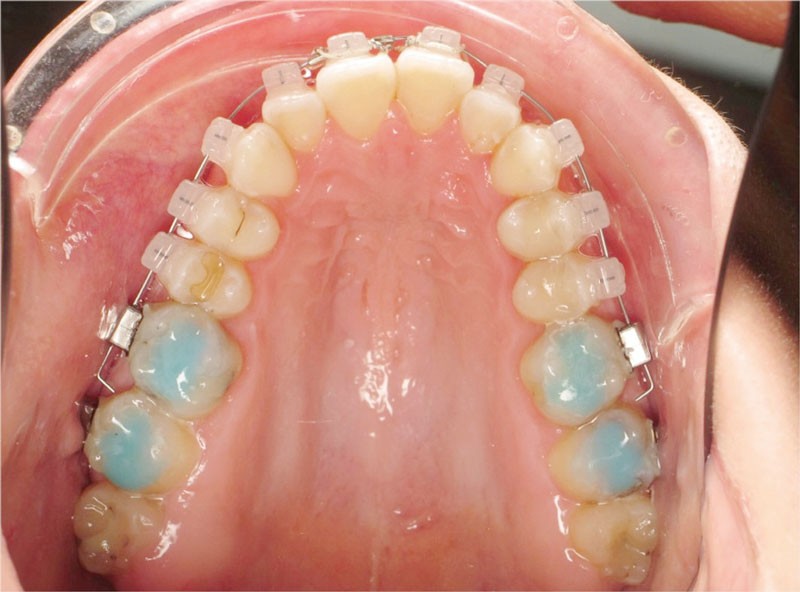

Des surélévations postérieures par cales sont posées et nous avons prévu un port d’élastiques précoce 23 heures sur 24.

Les empreintes ont été réalisées en sillcone wash technique et adressées au laboratoire Insignia. Actuellement, nous réalisons ces empreintes à l’aide de la caméra intra-orale Lythos et la fiche patient est initialement créée sur la caméra. Le transfert des empreintes au laboratoire est immédiat et le risque d’erreurs considérablement réduit (fig. 4 à 6).